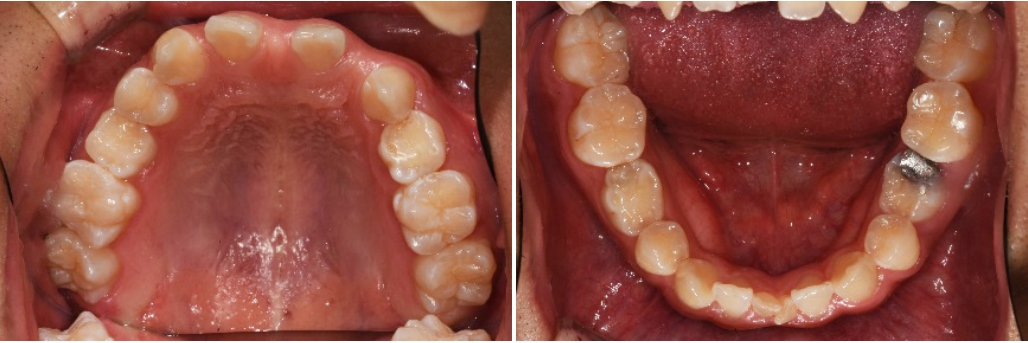

이 환자는 상악 양측 측절치와 양측 제1, 2 소구치, 하악 양측 제1, 2소구치, 양측 중절치의 결손을 가진 multiple congenital missing 환자입니다만 계속적 권유에도 불구하고 임플란트를 통한 전치부의 spacing 해결만을 원하였습니다.

때문에 상악에서만 부분교정을 통해 측절치 임플란트 식립 공간을 확보하기로 하였으며 동시에 상악 중절치의 반대교합 수정을 하기로 하였습니다.

양측 견치의 회전을 수정할 필요가 없고 중절치 이동을 위한 고정원으로 사용하기 위해 견치의 움직임을 최소화하였습니다.